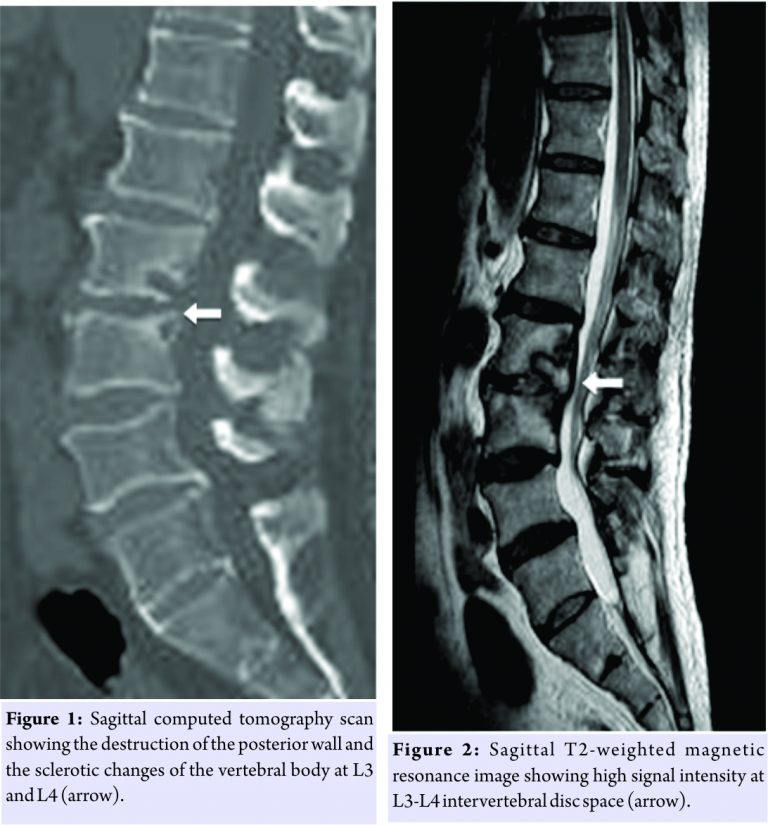

A 73-year-old man with a history of diabetes mellitus was admitted to our hospital with a 5-month history of severe low back pain. On admission, he had no fever, and neurological evaluation was within normal limits. A lateral radiograph of the lumbar spine demonstrated intervertebral disc space narrowing with indistinct end plates at the L3-L4 level. A computed tomography (CT) scan revealed destruction of the posterior wall and sclerotic changes of the vertebral body at L3 and L4 (Fig. 1). T2-weighted magnetic resonance imaging (MRI) showed a high signal intensity area at the L3-L4 intervertebral disc (Fig. 2). His white blood cell count was 8400/µL, and C-reactive protein level was 2.37 mg/dL. Initially, we suspected pyogenic spondylitis and encouraged him to rest with a lumbosacral corset. Percutaneous posterolateral endoscopic debridement and irrigation of the intervertebral disc according to Ito’s procedure [4] were performed 6 days after admission. Surgery was performed with the patient in the prone position, using the Yeung endoscopic spinal system (Richard Wolf Medical Instruments, Vernon Hills, IL, USA). A micro endoscope was obliquely inserted at 45° to the vertical line, targeting the center of the disc space. Aggressive debridement of the infected disc material and saline irrigation was performed. A 3-mm diameter drain tube was placed in the disc space, and drainage continued for 7 days after the surgery. After the surgery, he received antibiotics starting with 1 g cefazolin empirically administered intravenously 3 times daily for 10 days. Blood and urine samples remained sterile. Although gradual improvement was seen in the inflammatory response, his low back pain continued. Intraoperative sample culture results tested with the Rap ANA II SYSTEM (Norcross, GA, USA) and were positive for P. micros, which is sensitive to piperacillin. Therefore, we changed the antibiotics to 1 g piperacillin intravenously 3 times daily for the next 35 days. After that, he developed a rash all over his body. We suspected drug eruption and changed the antibiotics to 600 mg clindamycin intravenously twice daily for the next 12 days. Because his low back pain gradually subsided and inflammatory response became negative 8 weeks after the surgery, we prescribed 200 mg oral minocycline daily for 7 months. He was discharged 2 months after the surgery. 8 months after initiation of treatment, radiographs and CT scans of his lumbar spine showed sclerotic endplate changes, and T2-weighted MRI revealed restored signal intensity at the L3-L4 intervertebral disc. He reported no low back pain and had no signs of infection recurrence.